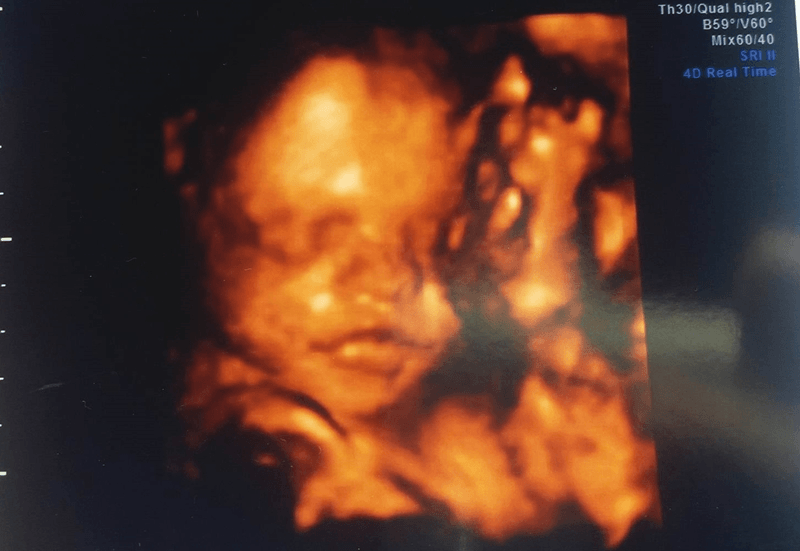

Śliczny